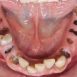

Interdisciplinary Treatment of Patients with Deep Overbite and Parafunctional Activity

Bruxism is defined as parafunctional grinding of teeth and due to the excessive wear of the posterior teeth, patients with long-standing bruxism often have pathological deep overbite. For many decades, treatment of bruxism and deep overbite was focused on reshaping the bite for achieving an occlusion free of deviations. Despite large efforts, the management of bruxism and subsequent deepening overbite was not obtained.